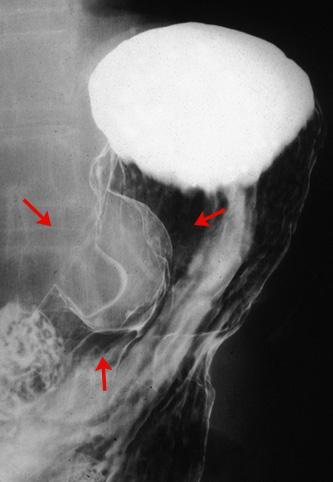

疾患(病理主体)の分類良性非上皮性腫瘍/神経系腫瘍

部位(臓器別)胃(部位)/体部

検査方法X-P

腫瘍の肉眼分類1型(腫瘤型)/

病変の最大径(ミリ)35〜40